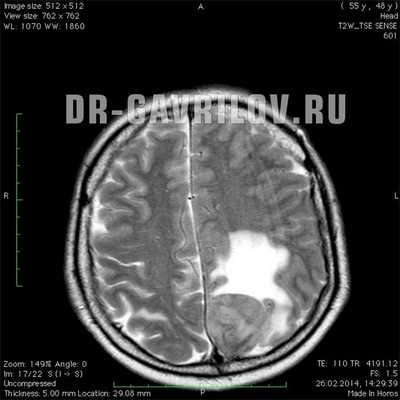

На фото МРТ менингиомы головного мозга

Наиболее информативными и точными методами диагностики менингиомы являются компьютерная томография (КТ) и магнитно-резонансная томография (МРТ). Как правило, данные исследования проводят с контрастированием. КТ и МРТ позволяют определить размер опухоли, её локализацию, степень поражения окружающих тканей и возможные осложнения.